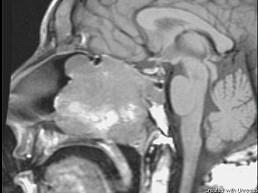

问题 15岁,男性,渐进性鼻塞1年余,MRI扫描如图所示,请选择最可能诊断 ( )

选项 A、鼻咽部囊肿 B、鼻咽癌 C、鼻咽部脓肿 D、脊索瘤 E、鼻咽部纤维血管瘤

答案 E